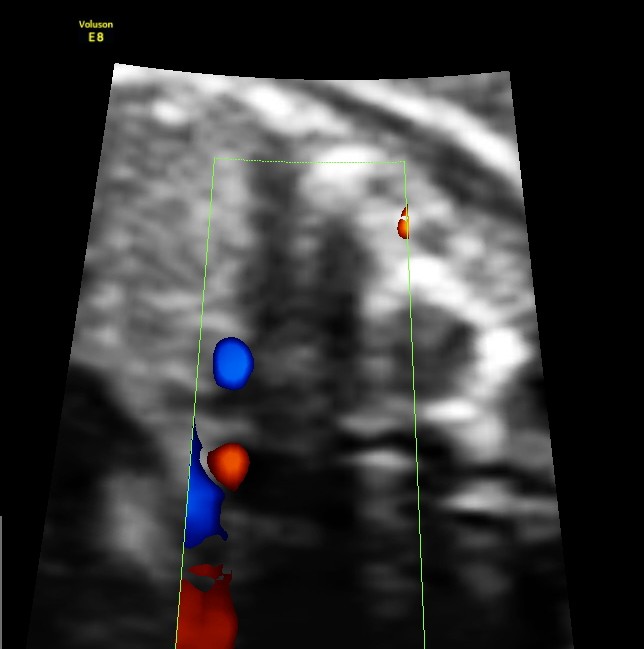

Particular to the diagnosis of Left isomerism or polysplenia syndrome is the demonstration of inferior vena caval interruption with azygos continuation.

double vessel sign seen in front of spine

double vessel sign seen behind the heart

1. double vessel sign of aorta and azygos vein running side by side , with azygos slightly posterior,